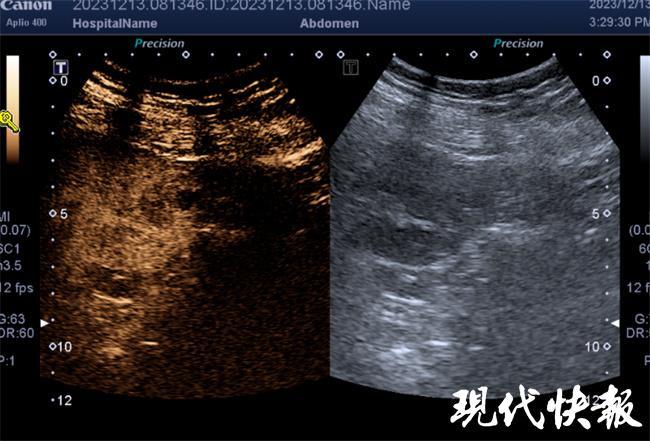

经学习讨论结合学习文献,专家们一致认为最新英文文献中成人应用的CT或超声引导下射频消融是手术切口最小、对患儿最有益的治疗方式。泌尿外科立即联合放射科、超声科、麻醉科、心内科共同讨论具体治疗方案,决定采用无辐射的超声造影引导下射频消融术。

术前泌尿外科与放射科、超声科提前为患儿进行了苏州大学附属儿童医院首例超声肾脏占位六氟化硫微泡静脉造影,精准计算造影剂起效、代谢时间,讨论术中可能出现情况,并于手术前一天与放射科、麻醉科、心内科共同讨论围手术期血压监测方案。

在术前充分全面准备后,医院于12月20日邀请上海第十人民医院超声介入科余松远主任医师现场指导,泌尿外科术中于肾盂内置入导管注入冰生理盐水,局部降温避免副损伤,放射科精准穿刺进行射频消融,在麻醉科的保驾护航下最终顺利实施了全球范围内首例儿童肾素瘤超声造影引导下肾肿瘤射频消融术。